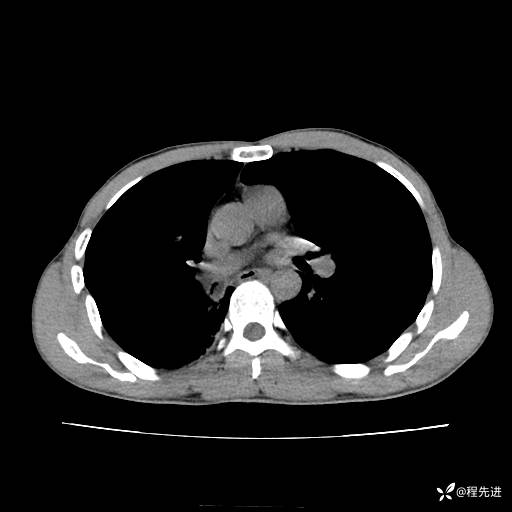

患者性别:男

患者年龄:49岁

主诉:咳嗽、胸痛1周

简要病史:1周前受凉感冒后开始出现咳嗽症状,阵发性连声咳,痰多,黄白痰,不易咳出,伴胸痛、气紧、胸闷,右侧为主,活动用力、呼吸时胸痛明显,曾在当地诊所贴敷膏药仍疼痛

体格检查:T:36.3 ℃ P:80 次/分 R:20 次/分 BP:120/88 mmHg,指脉氧饱和度97%,意识清晰,呼吸平稳,右侧第二、三肋骨压痛,可见膏药贴敷,皮肤无异常,双肺呼吸音粗,未闻及干湿性啰音。心率80次/分,节律整齐,无杂音。腹平软,全腹无压痛无反跳痛

临床诊断:社区获得性肺炎

CT平扫: